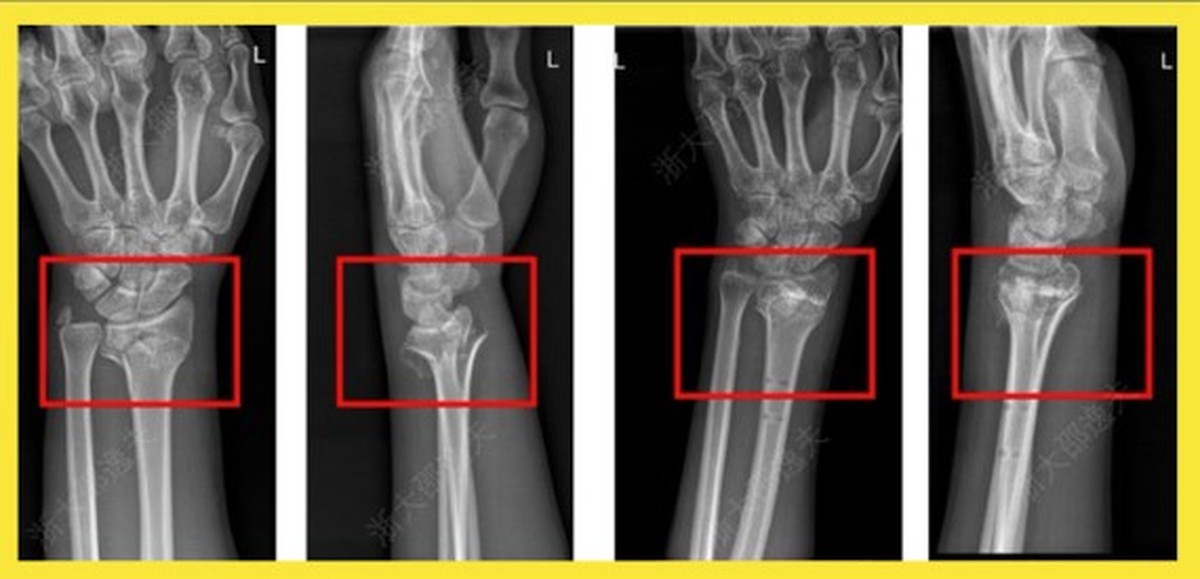

China diz ter revolucionado a ortopedia com ‘cola óssea’ que resolve fraturas ‘em minutos’